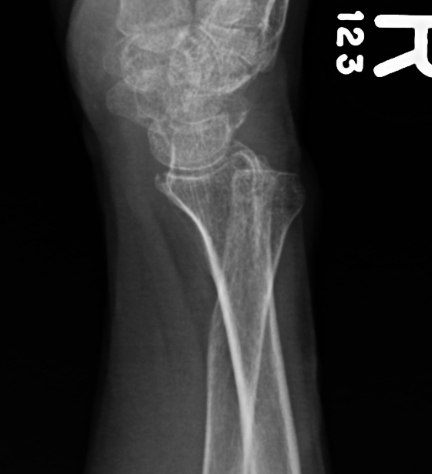

Galeazzi fracture

Galeazzi fracture with DRUJ disruption

Incidence of DRUJ instability after radius ORIF

Rettig et al J Hand Surg Am 2001

- 40 patients with Galeazzi fracture dislocations

- DRUJ instability after radius ORIF

- Type 1: radius fracture < 7.5 cm to articular surface: 55% DRUJ instability

- TYpe II: radius fracture > 7.5 cm to articular surface: 6% DRUJ instability